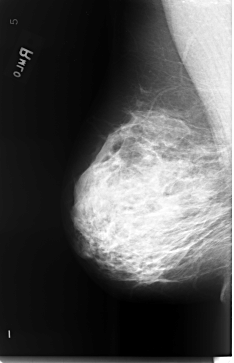

B_3470_1.RIGHT_MLO

RIGHT_MLO LINES 5808 PIXELS_PER_LINE 3736 BITS_PER_PIXEL 12 RESOLUTION 50 NON_OVERLAY